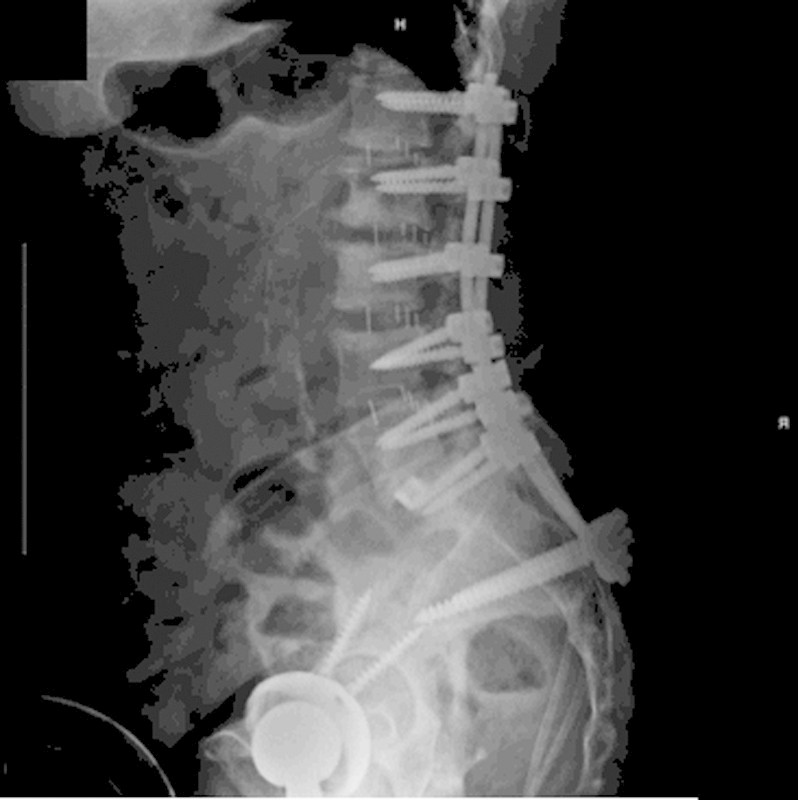

研究设计案例报告。目的本研究的目的是提出一个不寻常的情况下,59岁的妇女与复发的无菌术后血清肿。方法术后观察1例患者在创面闭合前先在软组织内放置预防性万古霉素粉2 g (1 g与后外侧骨融合术联合使用,1 g放置于软组织内)进行多节段腰椎前后路融合术的并发症或不良反应。在初始手术后的6个月内监测患者的进展。术后6周,患者摔倒,疼痛加重。磁共振成像、计算机断层扫描和x线显示骶骨骨折移位,大量硬膜外积液,腰椎手术部位硬膜囊严重受压(L3-5)。结果根据上述影像学检查和患者进行性神经功能缺损,在6周的随访中明显需要紧急手术干预。引流和检查硬膜外积液,同时治疗移位性骶骨骨折(S1-S2)。患者术后过程平稳,背部疼痛和神经功能障碍得到缓解;然而,复发的硬膜外积液需要连续穿刺混淆了患者的临床表现。结论由于该血肿的复发性不常见,其液体收集和形成的原因尚不清楚。由于缺乏骨形态发生蛋白的使用,并且很少有可解释的混杂变量,对局部万古霉素粉末的急性过敏反应是可能的病因。建议对更大的患者群体进行分析,比较预防性万古霉素粉末的术后不良反应。

Study Design Case report. Objective The objective of this study was to present the unusual case of a 59-year-old woman with a reoccurring sterile postoperative seroma. Methods A patient was observed postoperatively for any complications or adverse side effects resulting from an initial multilevel anterior/posterior lumbar fusion surgery where 2 g (1 g combined with the bone graft used for posterolateral fusion and 1 g placed in the soft tissues) of prophylactic vancomycin powder was placed within the soft tissues posteriorly before wound closure. The patient's progress was monitored through 6 months following the initial procedure. Six weeks postoperatively, the patient sustained a fall and had increased pain. Magnetic resonance imaging, computed tomography, and X-rays demonstrated a displaced sacral fracture, a large epidural fluid collection, and severe compression of the thecal sac at the lumbar operative sites (L3-5). Results On the basis of the aforementioned imaging studies and the patient's progressive neurologic deficit, it was apparent at the 6-week follow-up that emergent surgical intervention was necessary. Drainage and examination of an epidural fluid collection along with treatment of a displaced sacral fracture (S1-S2) were performed. The patient had an uneventful postoperative course with resolution of her back pain and neurologic deficit; however, recurrence of the epidural fluid collection requiring serial aspirations confounded the patients' clinical presentation. Conclusions With the recurrent nature of the seroma being unusual, the cause of the fluid collection and formation is undetermined. With lack of bone morphogenetic protein usage, and few confounding variables accountable, an acute allergic response to topical vancomycin powder is a possible etiology. Analysis with larger patient populations comparing postoperative adverse effects of prophylactic vancomycin powder is recommended.